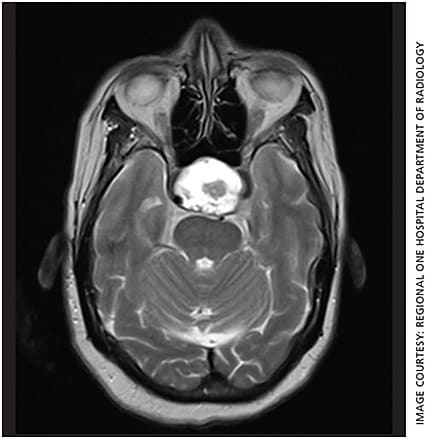

Given the differential diagnosis, the following labs and imaging studies were ordered: rapid plasma reagin and fluorescent treponemal antibody absorption tests to evaluate for syphilis, angiotensin-converting enzyme to evaluate for sarcoidosis and vitamin B12 to evaluate for a nutritional deficiency. All laboratory studies were within normal limits. MRI of the brain/orbits showed a cystic and solid 3.0 x 3.8 x 3.1-cm sellar-suprasellar mass with enlargement of the sella and invasion of the cavernous sinus, partial encasement of the cavernous segment of the internal carotid arteries and uplifting of the optic chiasm (Figure 2). Differential diagnosis for the lesion includes craniopharyngioma and pituitary macroadenoma.